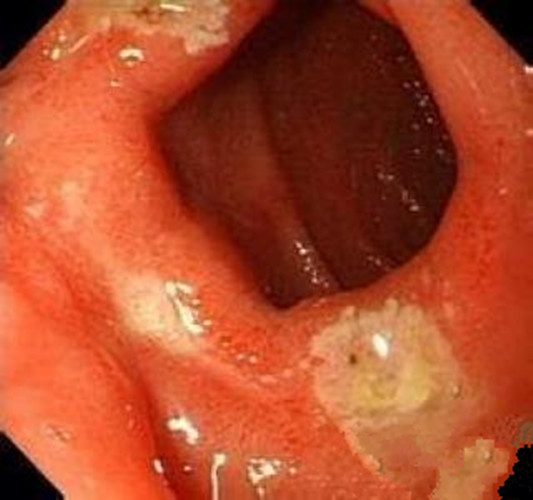

淺表型慢性胃炎

淺表型慢性胃炎萎縮